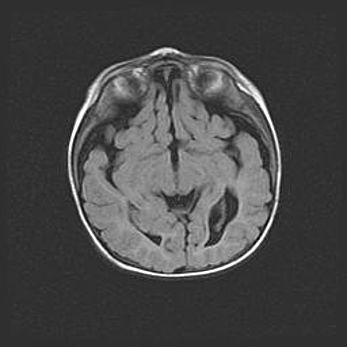

Наружная гидроцефалия с возможной атрофией височных областей.

Возраст: 28 дней

Вес: 3670 г

Пол: мужской

Окружность головы: 38 см

Срок гестации: 40 недель

Гидроцефалия головного мозга у новорожденных – это заболевание, которое характеризуется скоплением избыточного количества спинномозговой жидкости в желудочковой системе головного мозга в результате затруднения её перемещения от места выработки к месту поглощения в кровеносную систему или вследствие нарушения абсорбции. При открытой наружной форме гидроцефалии у новорожденных расширяются и переполняются субарахноидные пространства.

При нормотензивных  формах,  которые,  как  правило,  являются  следствием  перенесенных ишемических  повреждений  паренхимы  мозга,  возможно  сочетание микроцефалии  с нормотензивной гидроцефалией. В основе данных изменений лежит атрофия больших полушарий с преимущественной  локализацией  в  лобно-височных  областях.